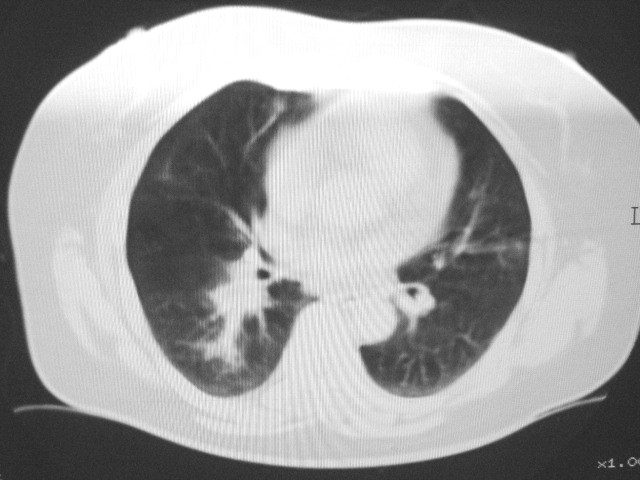

以下是引用清清楚楚在2007-8-28 7:13:00的发言:[br]右肺下叶可见斑片状高密度影,边缘模糊;右肺中叶内侧段及左肺舌段亦可见小斑片状模糊影。[br]考虑双肺感染,建议抗炎治疗后复查。

以下是引用天南地北在2007-8-27 23:49:00的发言:[br]右肺下叶可见斑片状高密度影,边缘模糊;右肺中叶内侧段及左肺舌段亦可见小斑片状模糊影。[br]考虑双肺感染,建议积极抗炎治疗后复查。

以下是引用天南地北在2007-8-27 23:49:00的发言:[br]右肺下叶可见斑片状高密度影,边缘模糊;右肺中叶内侧段及左肺舌段亦可见小斑片状模糊影。[br]考虑双肺感染,建议抗炎治疗后复查。

以下是引用难听在2007-8-28 13:17:00的发言:[br]右肺下叶背段支气管狭窄,是否可以考虑新生物伴阻塞性肺炎.请大家帮帮忙,这个病人是卫生局长的丈母娘.惹不起啊.